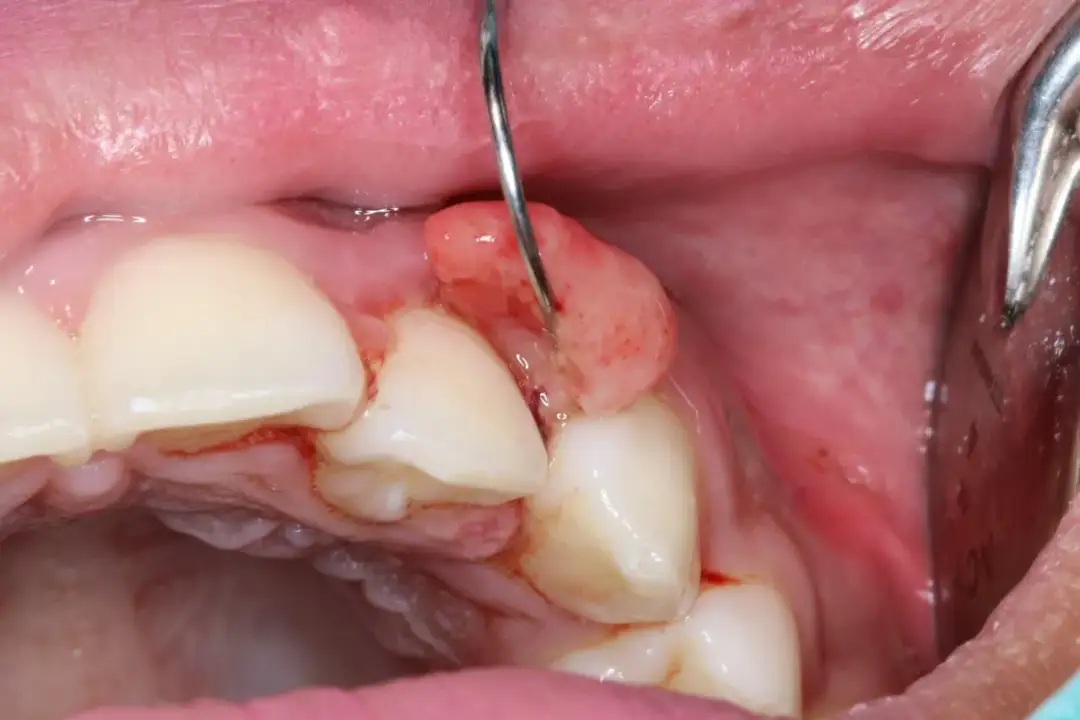

Skuteczne metody na spuchnięte dziąsła, domowe sposoby i porady zdrowotne, które pomogą złagodzić objawy i poprawić zdrowie jamy ustnej.